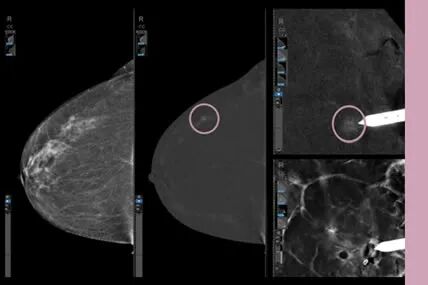

乳腺断层摄影(DBT)更早期发现病灶

相较于以往的乳腺机设备,全新乳腺机创新性地使用了GE第二代ASiR DBT迭代断层技术,首次将应用于CT影像检查中的“迭代断层”应用到乳腺机中,实现了更高图像分辨率和更低射线剂量。DBT 从设计原理上能减少或消除乳腺组织重叠和结构噪声的影响,提高病变的检出及肿块边缘的显示,尤其对致密型腺体背景下的非钙化病灶形态(如:肿块伴毛刺、结构扭曲)评估具有重要价值。